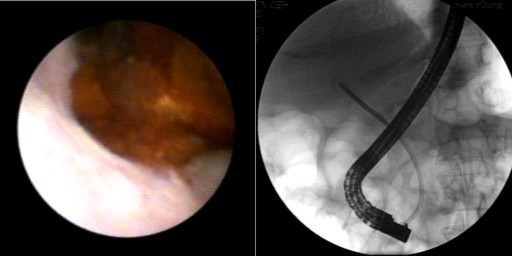

A 68-year-old male with history of orthotopic liver transplantation seven months before for hepatitis C induced cirrhosis presented for a routine follow-up visit. The patient did not report any complaints and physical exam was normal. Routine laboratory evaluation revealed a cholestatic liver enzyme elevation (alkaline phosphatase 580 IU/L, reference range: 80-130 IU/L), total bilirubin 2.3 mg/dL (reference range: 0.7-1.2 mg/dL) with normal aminotransferases and normal prothrombin time. Hepatitis C RNA was undetectable. Ultrasound demonstrated normal common bile duct (C) diameter with normal Doppler flow. Liver biopsy showed no acute rejection, but with suggestion of cholestasis. Endoscopic retrograde cholangiopancreatography (ERCP) with occlusion cholangiogram showed multiple linear filing defects in the proximal hepatic duct proximal to the anastomosis with extension into the intrahepatic system (Figure 1). Balloon failed to remove the filling defect. A single operator choledochoscope was then passed into the common hepatic duct for diagnostic visualization and possible therapeutic purpose. A dark brown tubular structure was seen resembling a cast of the bile duct (Figure 2). Using a basket, the distal aspect of the cast was secured and a 6 cm long cast was successfully removed in a single piece (Figure 3). Cholangiogram showed improvement with excellent biliary drainage both fluoroscopically and endoscopically. Liver function tests subsequently normalized. Patient followed up to a period of 14 months without recurrence of symptoms.

Figure 2. Direct visualization of the biliary cast and fluoroscopic location using single operator choledochoscope. |